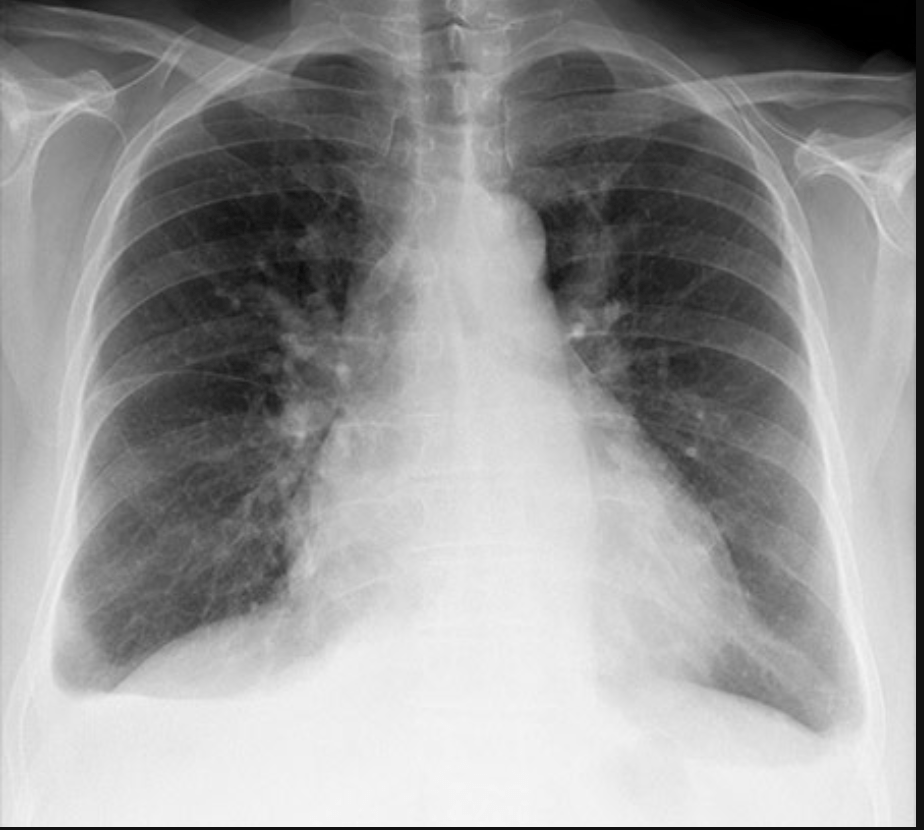

• Lets take this image for example.

• What do we see in it?

What do we look for in a CXR?

• How about this one?